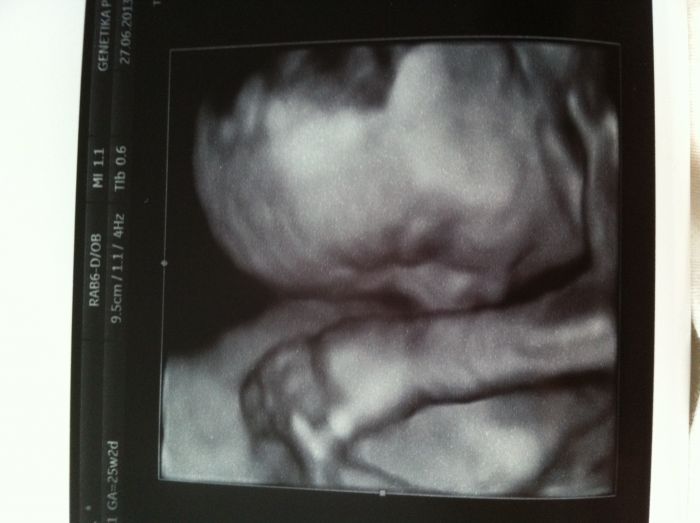

Ja si myslím, ze kdyz se mimi poradne oblečeni, muze ven hned od zacatku, hlavne se vyhýbat uzavřeným prostorům, ale venku to nevadi. jen s tím oblekanim je to trosku alchymie :-) ale ja prosazovala pravidlo raději více nez méně, to hrozily nanejvýš potnicky :-) Nejaka z holcin se ptala na jméno, jestli Nela nebo Sofie, za me určitě Nela ;-) Sofie je krasne jméno, ale je jejich ted strašně moc, ve školce máme samou Sofinku a samého Filipka, takže za me Nela, jednoduche, krasne, lehce zdrobnelinkovatelne :-) Za to my s tema jmenama jsme na štíru :-( Krystufek chce Vincenta a nehne se od nej... Další alternativa je Erik, ale nepřijde vám to takove spis pro obcany pobirajici soc. dávky ve velkém? Muj Ondrašek je v pozadí, no... Líbí se mi ještě Šimon, ale toho blízka kamarádka, malýmu se líbí ještě Jonáš ( to se mi zda byt divny) a Štěpán, 2 kamarádky maji Stepany, takže to asi taky ne, ach jo, asi počkám, az se narodí a pak se rozhodnu :-) Jinak jsme byli včera na 3 D , malej se porad schovával, ale jsme ok, všechny orgány velikostne o funkčně ok, jedna fotka se podařila, video jsme ani nechtěli, kdyz nebylo nic vidět, tak jsme za trictrvtehodinove snažení dali nakonec 100 Kč, což celkem jde, ale musím říct, ze jsem porovnávala tu fotku s Krystufkovo fotkou, hned po narozeni, no a jsou úplne stejni, takže cela ja :-) doufám, ze bude mit aspon barvu vlásku a ocicek po Ladovi :-) Krystufek ma černé oči a hnede vlasy po me, přítel ma špinavý blond a modre oči, tak snad aspon něco z toho převezme :-) přála bych mu to moc :-) zkusím přiložit fotku...